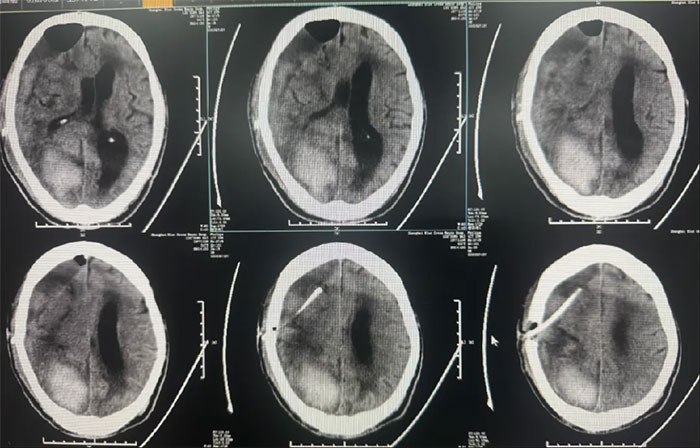

手术治疗:

硬脑膜下钻孔引流术(长程引流管),引流管自右侧锁骨下皮肤穿出引流;

2025-02-18(发病后17天);

手术情况:

患者病情复杂,选择在局麻下进行,术程顺利。

术后中线偏移明显改善,颅内压降低,停用脱水药物;